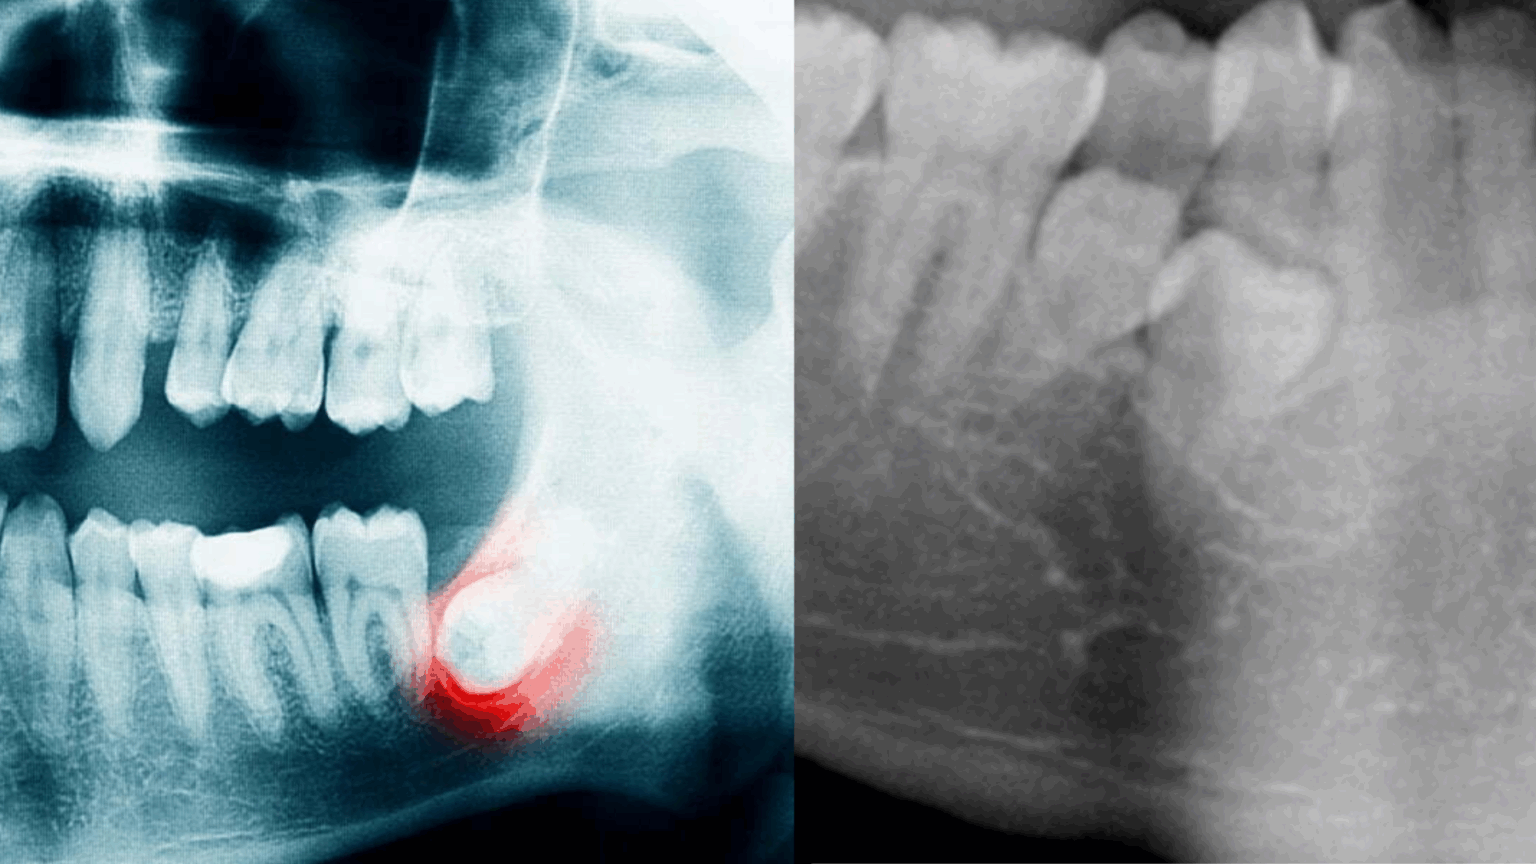

Як діагностується ретенція зубів?

Сучасна стоматологія використовує кілька високотехнологічних методів діагностики для виявлення ретенованих зубів. Ортопантомограма, або панорамний знімок, дозволяє отримати повну картину розташування зубів у щелепі та виявити порушення їх прорізування. Для оцінки прикусу часто застосовується телерентгенограма — цей метод допомагає лікарю визначити положення щелеп та взаємозв’язок між зубами.

Найточнішим методом є конусно-променева комп’ютерна томографія (КПКТ), яка дозволяє з високою точністю визначити положення ретенованого зуба, оцінити його близькість до важливих анатомічних структур і виявити можливі ризики, зокрема пошкодження коренів сусідніх зубів.